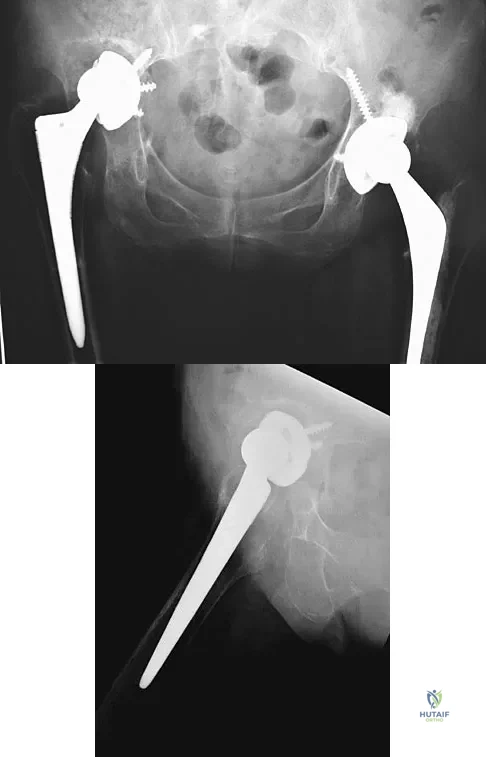

Figures 40a and 40b show the pre- and postoperative radiographs of an 82-year-old woman with bilateral hip pain who has had staged total hip arthroplasties. To minimize potential injury to the sciatic nerve at the time of surgery, the surgeon should